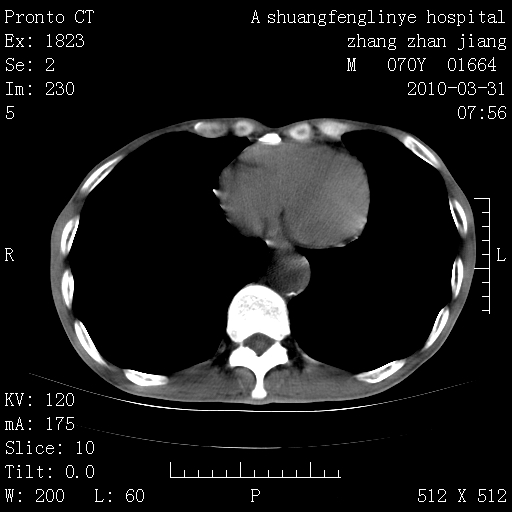

双上肺继发型tb并左上空洞形成,主动脉冠脉钙化。

1)两肺上叶继发性肺结核并左肺上叶空洞形成。2)冠状动脉及主动脉钙化。